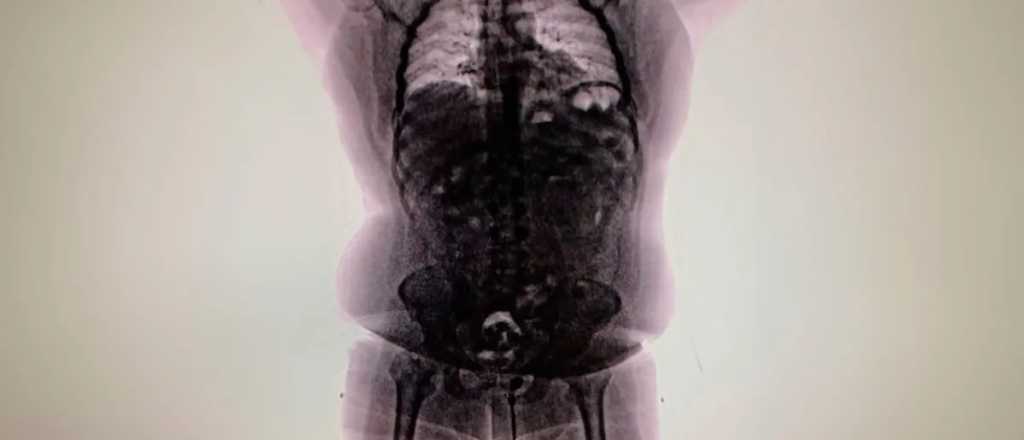

El escáner detectó las cápsulas que al ser extraídas en el hospital, descubieron que contenían drogas.

Un escáner corporal confirmó la presencia de cuerpos extraños en su interior. Morales García fue trasladado al Hospital de Ezeiza, donde evacuó las 90 cápsulas durante un período de cuatro días. En total, la carga contenía 698 gramos de cocaína.